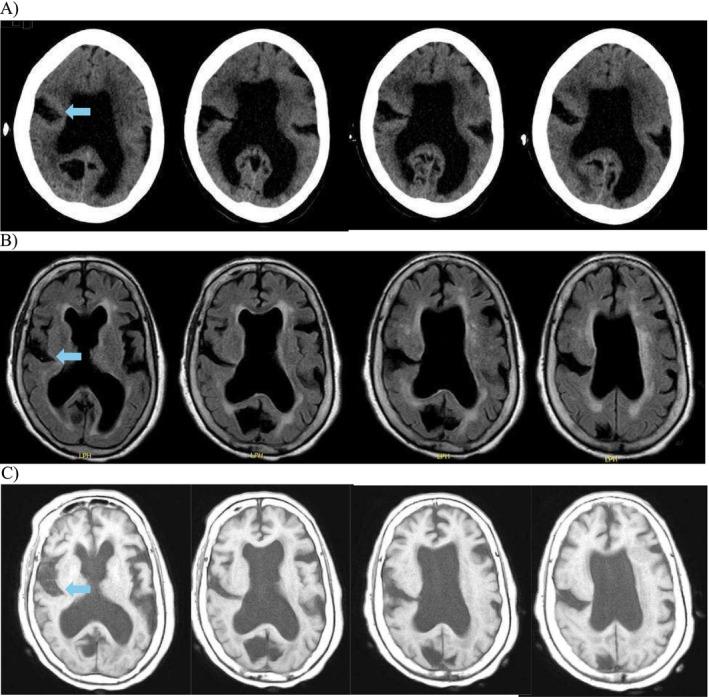

The variable clinical presentations of open lip schizencephaly can lead to misdiagnosis, as occurred in this case originally misdiagnosed as polio in the 1930s. This case demonstrates the possible presence of confirmation bias, as the original poliomyelitis diagnosis remained unquestioned despite developments in the fields of Radiology and Neurology.

开放性唇裂脑畸形的临床表现多样,可能导致误诊,就像本例在20世纪30年代最初被误诊为小儿麻痹症一样。该病例显示了确认偏误可能存在,因为尽管放射学和神经学领域有了进展,但最初的小儿麻痹症诊断仍未受到质疑。